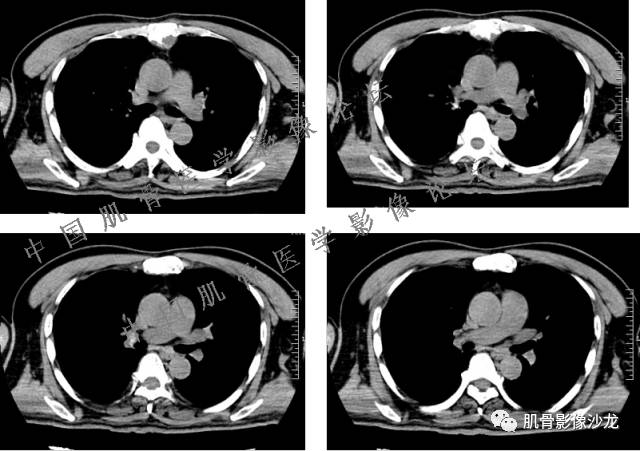

患者于2月前无明显诱因下出现腰骶部疼痛,夜间为重,逐渐加重伴左下肢麻木、疼痛,并有行走活动受限,在我院就诊,摄腰椎及骶髂部CT提示:腰椎骨质退变,腰3-4、4-5椎间盘膨出,骶髂关节炎。自用非甾体抗炎药无好转,再次来院就诊,门诊拟“骶髂关节炎”收住我科。病程无间歇性跛行,大小便正常。

专科检查:神清,脊柱无侧弯后凸畸形,椎体各节段无压、叩痛,双侧棘突旁无压痛,双侧骶髂关节压痛明显,左下肢放射痛,浅感觉较健侧减退,腰椎前屈后伸活动受限,膝、跟腱反射正常。

辅助检查:腰椎及骶髂部CT提示:腰椎骨质退变,腰3-4、4-5椎间盘膨出,骶髂关节炎。

雪舞 :第二例,位于骶骨,有骨质破坏并有软组织肿块,软组织肿块边界清

雪舞 :第二例挺难的,骨质破坏是溶骨性的,局部皮质中断,软组织肿块外缘光滑

雪舞 : 软骨肉瘤的发病率居原发性恶性骨肿瘤的第三位,其特点是肿瘤内具有软骨基质

1、软骨肉瘤可以有膨胀性骨质破坏(病例3,4),可以有溶骨性骨质破坏(病例2),局部皮质因为破坏变薄,中断 ;

2、软骨基质T2WI高信号,软骨小叶分叶状,也就会出现高老师提到的骨内膜扇贝形压迹。一般认为骨内膜扇贝形压迹超过骨皮质厚度的2/3是软骨肉瘤在长管状骨的特征性表现。如上图。3、软组织肿块或肿胀;

4、 钙化,环形,弓形,边缘模糊 ;

5、增强后进行性延迟,不均匀分割状强化, 会强化的纤维间隔,软骨小叶不会强化,关于老师们说到的钙化,软骨肉瘤不一定会有钙化 。